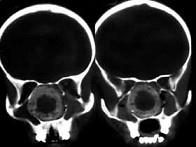

问题 女、14岁,渐进性鼻塞2年余,右眼肿痛数月,CT如图所示,应诊断为()

选项 A.筛骨骨肉瘤 B.筛骨骨纤维异常增殖症 C.筛骨软骨瘤 D.筛骨结核 E.筛骨骨化性纤维瘤

答案 E